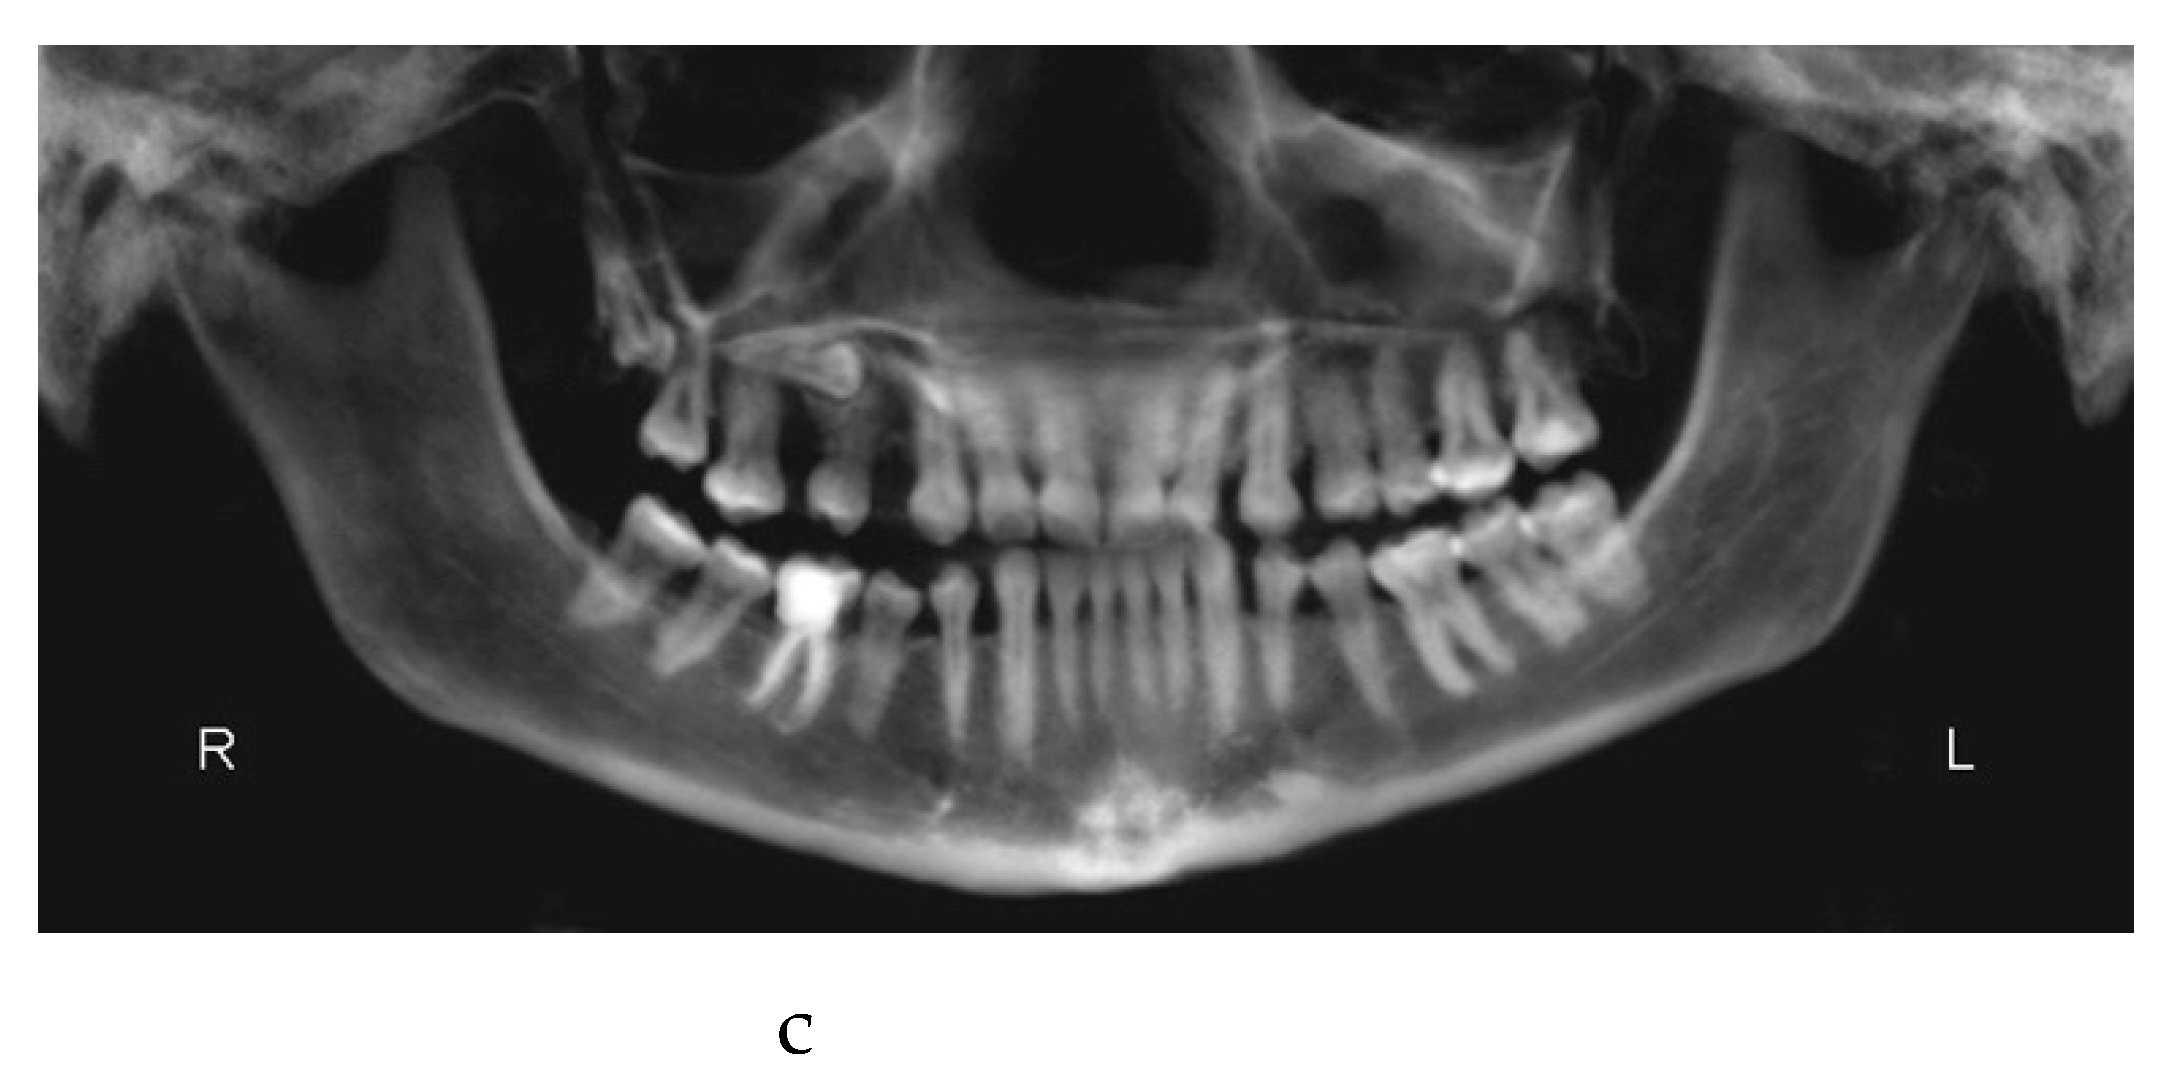

In October 2019 the patient underwent maxillofacial surgery to correct the severe skeletal malocclusion and relocate the bone bases in the right relationship. The combined surgery involved maxillary Le Fort I osteotomy [29]and mandibular reduction [30]. Skeletal fixation plates were then used to stabilize the bone segments [31].

One week later the post-surgical orthodontic treatment phase started (Figure 3a–c).

Figure 3. a: antero-posterior projection of the CBCT. b: lateral-lateral projection of the CBCT. c: panoramic projection of the CBCT.